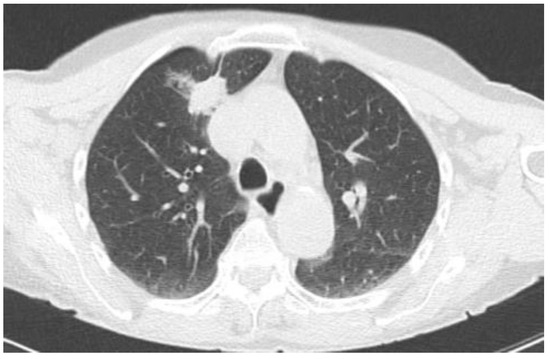

2.2.1. TIME 0: Lesion marking and SPECT Analysis